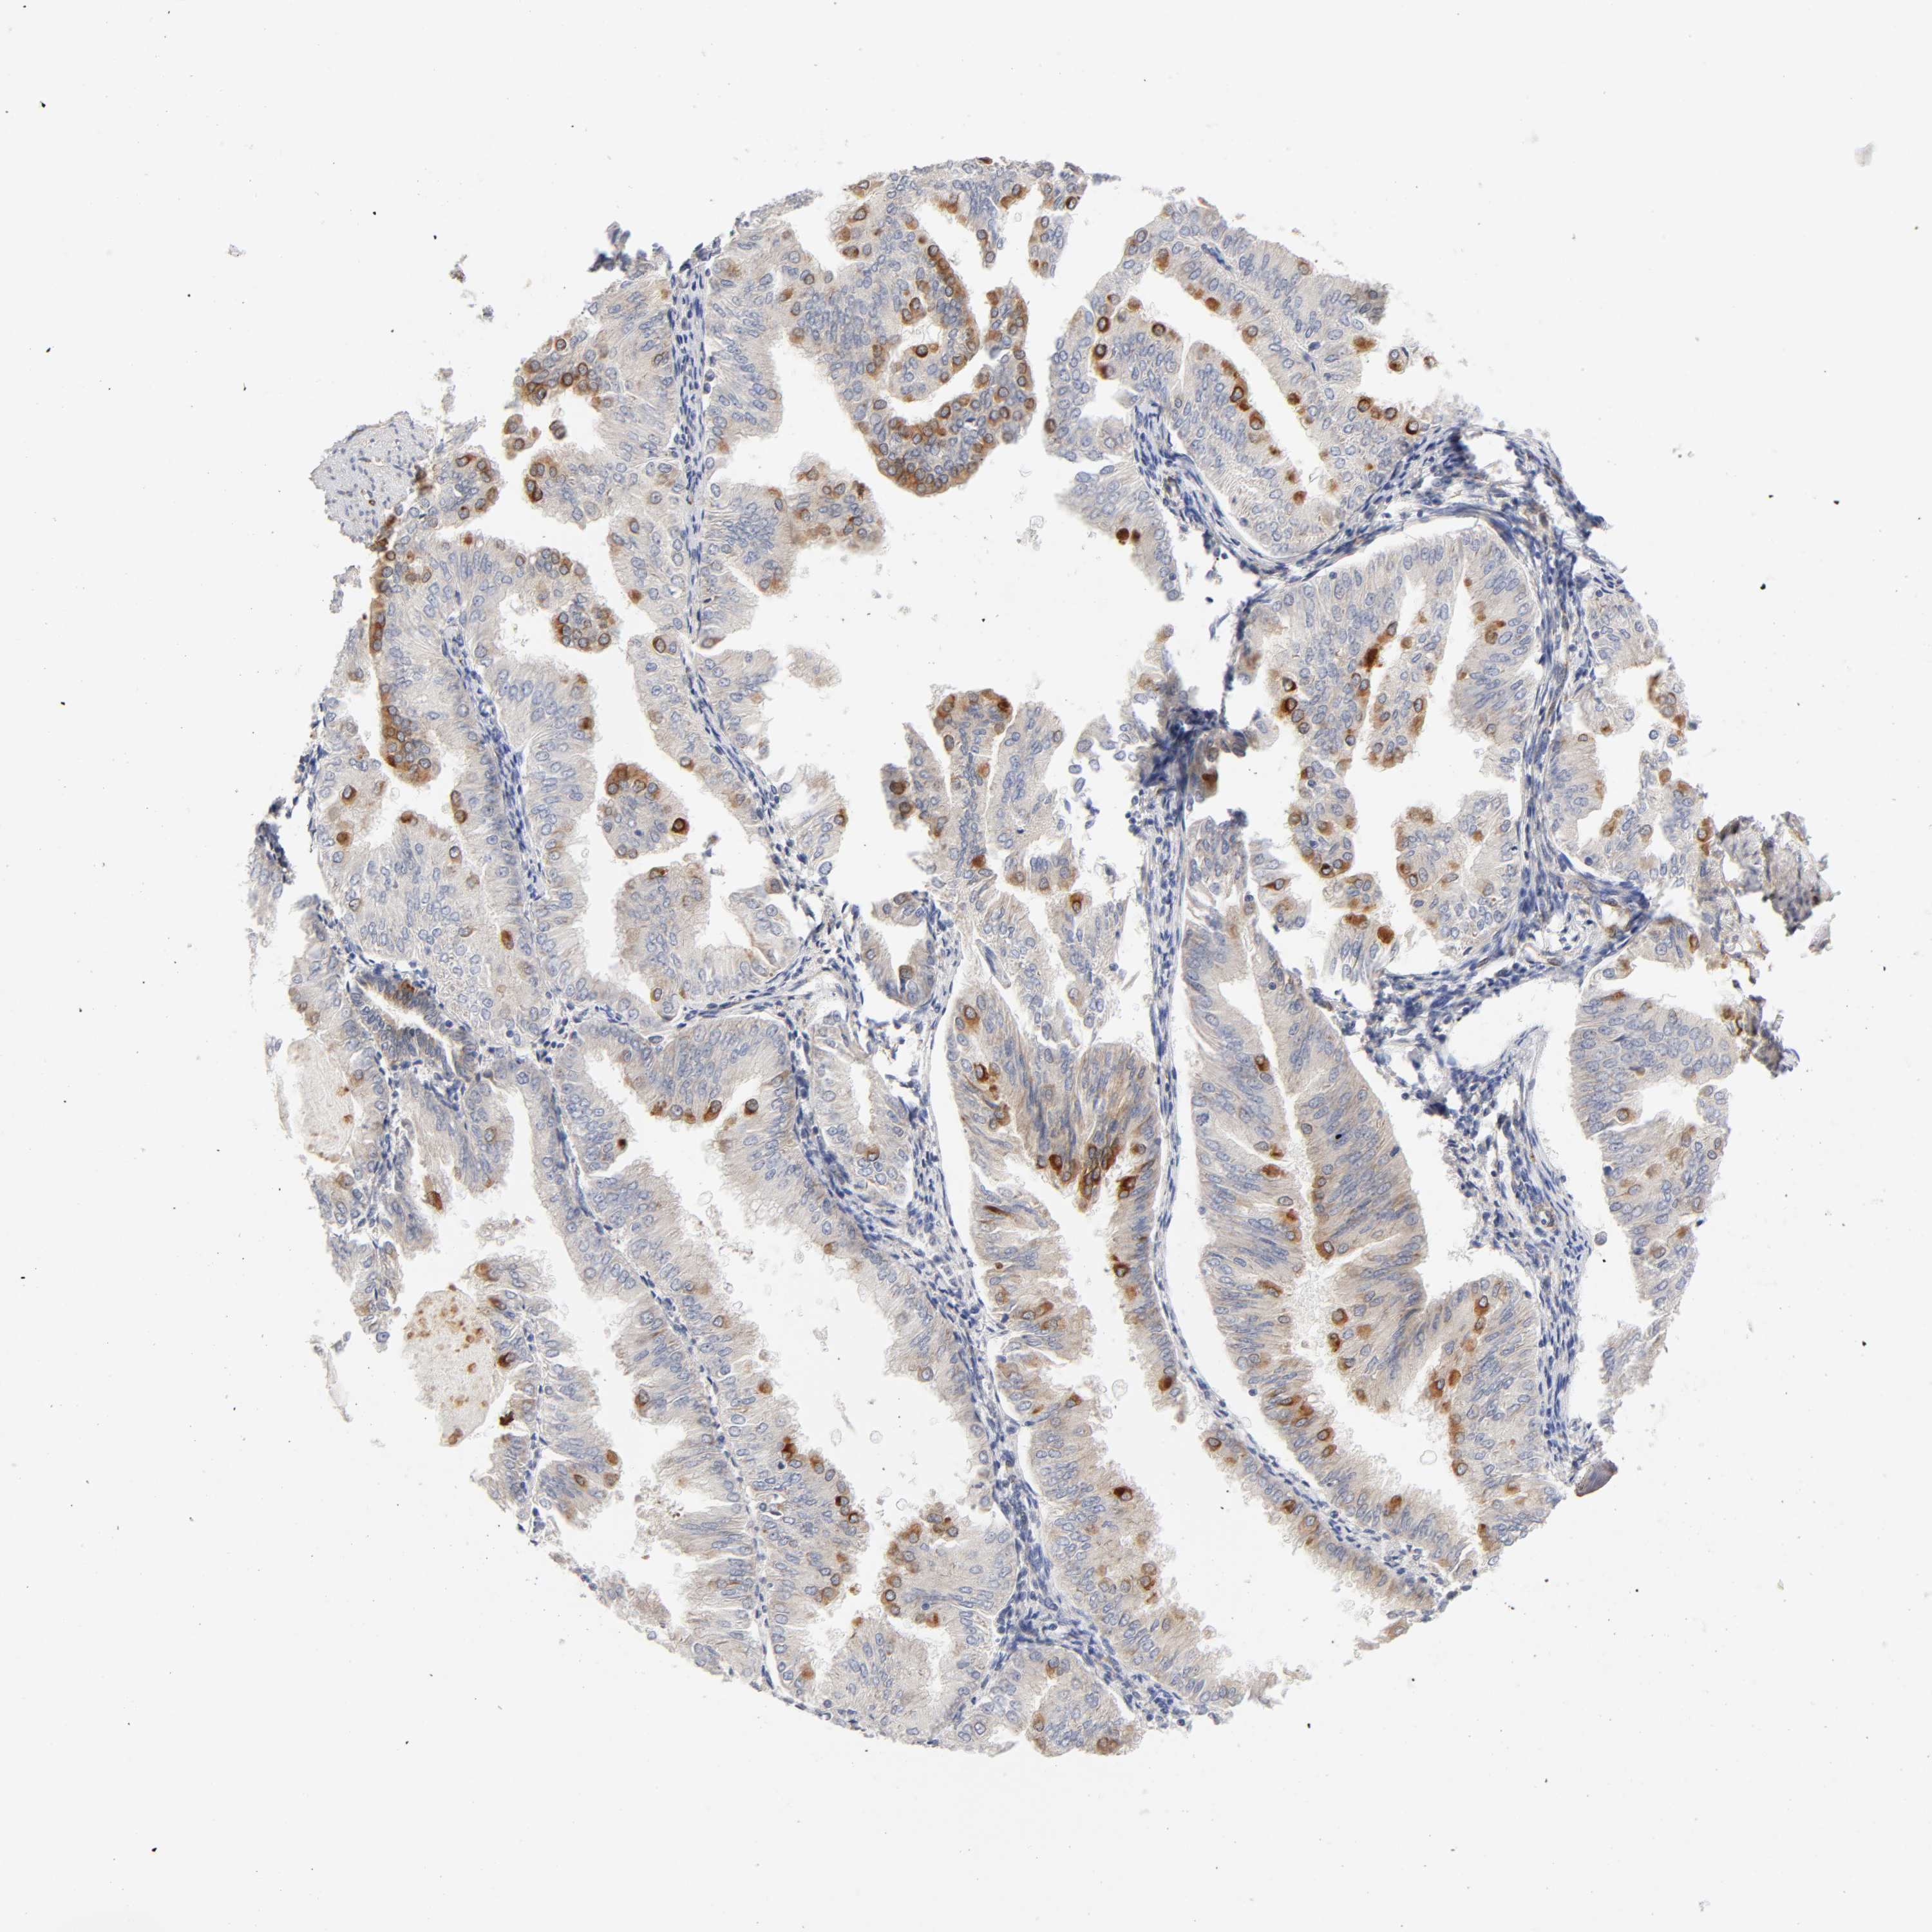

ENDOMETRIAL CANCER - Protein expressioni

A mouse-over function shows sample information and annotation data. Click on an image to view it in a full screen mode. Samples can be filtered based on level of antibody staining by selecting one or several of the following categories: high, medium, low and not detected. The assay and annotation is described here.

Note that samples used for immunohistochemistry by the Human Protein Atlas do not correspond to samples in the TCGA dataset.

Antibody stainingi

Antibody staining in the annotated cell types in the current human tissue is reported as not detected, low, medium, or high, based on conventional immunohistochemistry profiling in selected tissues. This score is based on the combination of the staining intensity and fraction of stained cells.

Each image is clickable and will lead to virtual microscopy that enables deeper exploration of all samples and also displays staining intensity scores, fraction scores and subcellular localization as well as patient and tissue information for each sample.

Antibody HPA010136

Antibody CAB004372

Staining

High

Medium

Low

Not detected

Intensity

Strong

Moderate

Weak

Negative

Quantity

>75%

75%-25%

<25%

None

Location

Nuclear

Cytoplasmic/membranous

Cytoplasmic/membranous,nuclear

Adenocarcinoma, NOS

Neoplasm, malignant, NOS